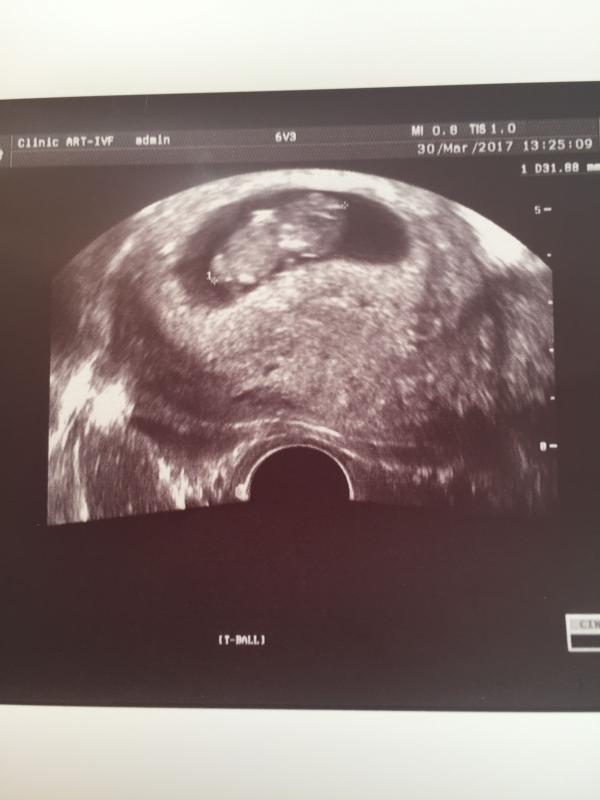

9 неделек, 5 дней 👏 Малышок уже 32 мм. Шевелит ручками, ножками!

@boo... точно! Даже прослезилась, когда он перебирал ручками )))

моя врач этот срок называет - стадия "мишки"🐻 и правда же на мишутку похожи)

У меня малыш на 7 неделе 34мм это геракл какой-то? 😄